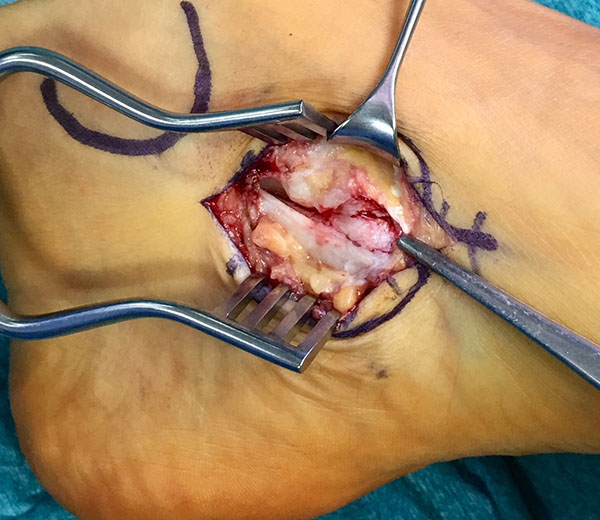

Resektion des Os tibiale externum bzw. Abtragung des medial prominenten Os naviculare cornutum und Refixation der Tibialis posterior Sehne am Os naviculare.

- Beim Herauslösen des Os tibiale externum sollten die kaudal zum Os naviculare verlaufenden Fasern der Tibialis posterior Sehne geschont werden. Somit wird eine vollständige Ablösung der Sehne vermieden. Grundsätzlich ist nur so viel des Sehnenansatzes abzulösen, wie zur Entfernung des Knochens notwendig.